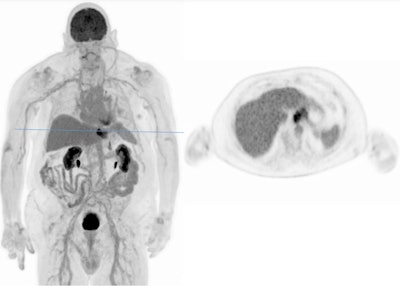

"You can follow this up with an FDG scan and use only a low dose and you can look for the mismatch. If you don't have a PSMA uptake in the lesion but then have an FDG uptake in the liver, this is known to be a negative predictor for the outcome," said Rominger, who has also set up a prospective study to compare ultralow-dose PET/CT on a Biograph Vision Quadra machine with a standard axial field-of-view (SAFOV) scanner in patients with lung cancer.

Low dose and ULD offer the possibility to perform multiple follow-up PET/CT scans on short-term follow-up. "You could even think about more and different radiotracers for further disease characterization."

![Ultralow-dose scan on Biograph Vision Quadra PET/CT (F-18 FDG in a healthy volunteer; weight: 86 kg; dose: 20.8 MBq [0.24 MBq/kg]).](https://img.auntminnieeurope.com/files/base/smg/all/image/2022/11/ame.2022_11_17_01_11_0740_2022_11_17_Rominger_image3.png?auto=format%2Ccompress&fit=max&q=70&w=400)

This comes with challenges, for instance having other tracers available. "From the technical point of view, it's possible. You can potentially think about screening at-risk population patients," he said.